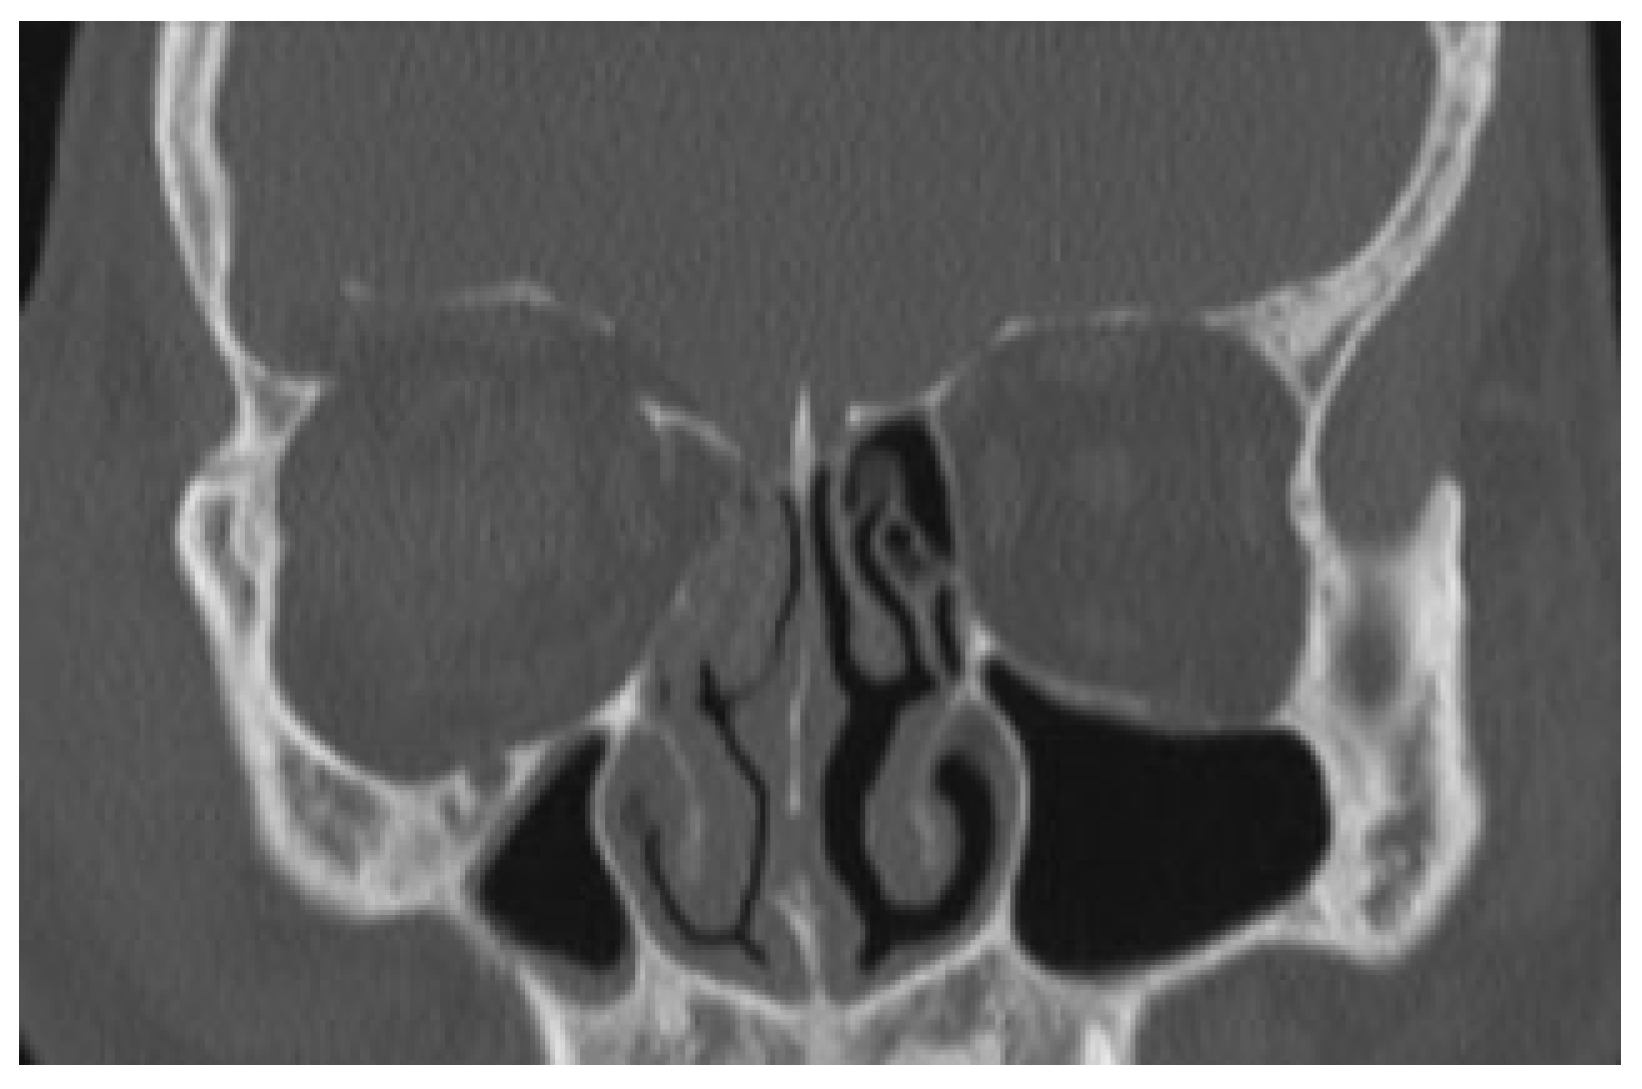

During follow-up, 2 weeks, 2.5, 9 months, and 1 year following the trauma, there were no functional or esthetic problems. CT scan obtained 1 year after trauma showed complete reposition of the left orbital roof fracture (

Figure 3 and

Figure 4).